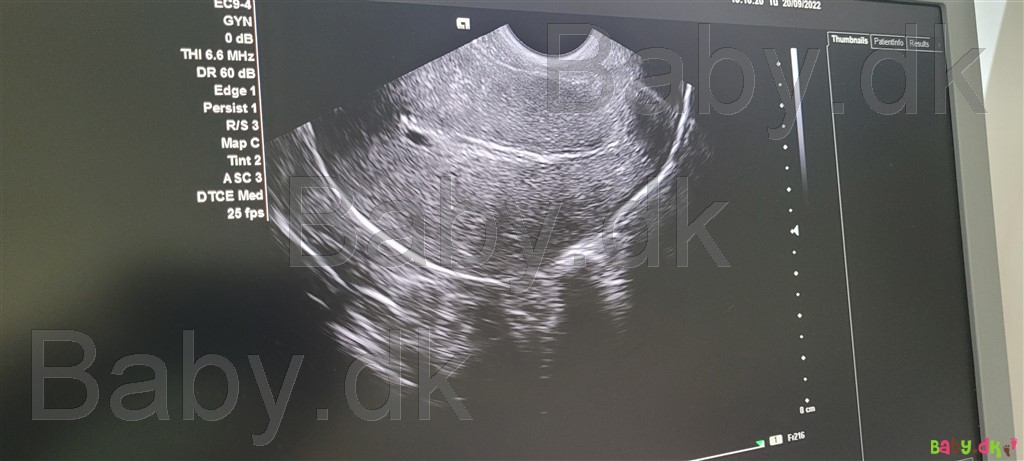

da jeg går til fertilitetsbehandling, ringede jeg og fortalte det. hun scannede mig d 20 og kunne se en blommesæk.